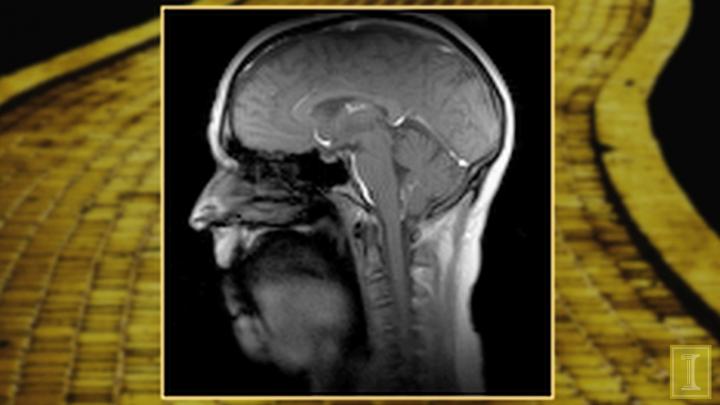

Thanks to the magnetic resonance imaging (MRI) capabilities in Beckman's Biomedical Imaging Center (BIC), Johnson can view dynamic images of vocal movement at 100 frames per second--a speed that is far more advanced than any other MRI technique in the world.

"Typically, MRI is able to acquire maybe 10 frames per second or so, but we are able to scan 100 frames per second, without sacrificing the quality of the images," said Brad Sutton, technical director of the BIC and associate professor in bioengineering at Illinois.

The dynamic imaging is especially useful in studying how rapidly the tongue is moving, along with other muscles in the head and neck used during speech and singing.

"In order to capture the articulation movements, 100 frames per second is necessary, and that is what makes this technique incredible," Johnson said.

"The technique excels at high spatial and temporal resolution of speech--it's both very detailed and very fast. Often you can have only one these in MR imaging," said Sutton. "We have designed a specialized acquisition method that gathers the necessary data for both space and time in two parts and then combines them to achieve high-quality, high-spatial resolution, and high-speed imaging."